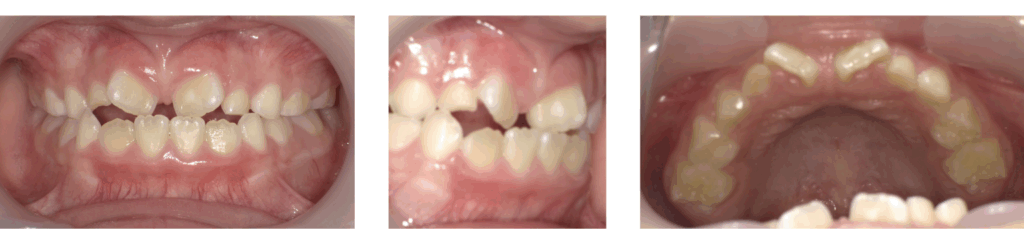

症例1:急速拡大装置とブラケット装置を併用した矯正治療

| 年齢 | 8歳 |

| 性別 | 女子 |

| 治療の理由(主訴) | 前歯がねじれていて、すきっ歯が気になる。 見た目をきれいにしたい。 |

| 治療方法 | 顎顔面矯正+ワイヤー矯正 |

| 治療期間 | 1年10か月 |

| 費用 | 66万円 |

治療前

顎顔面矯正

ワイヤー矯正

治療後